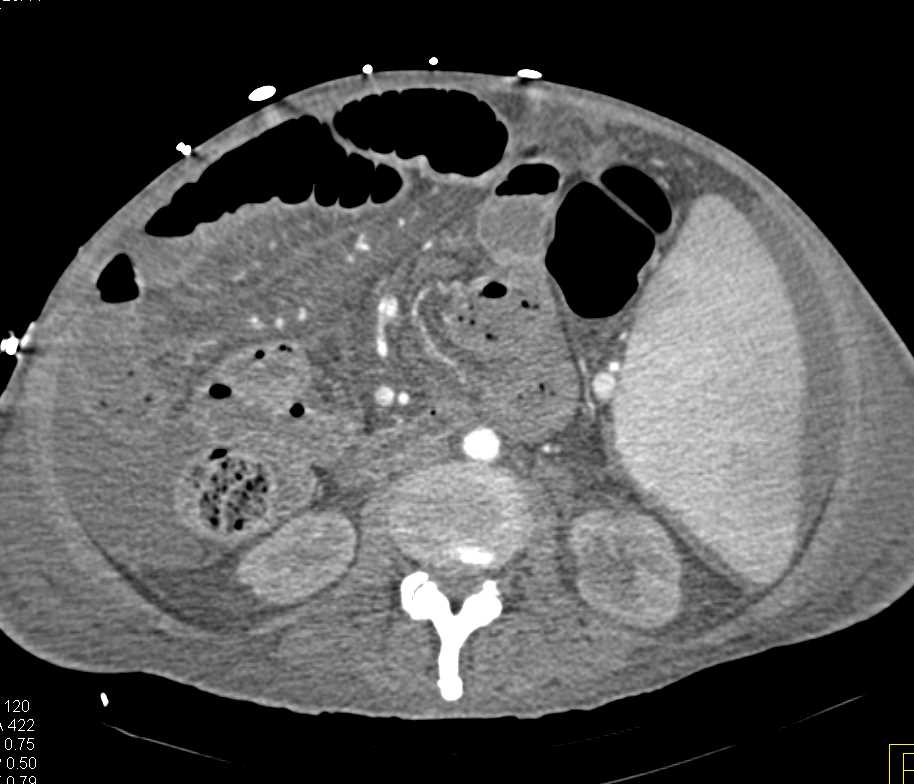

Duodenal Cancer with Stent and PV/SMV clot.